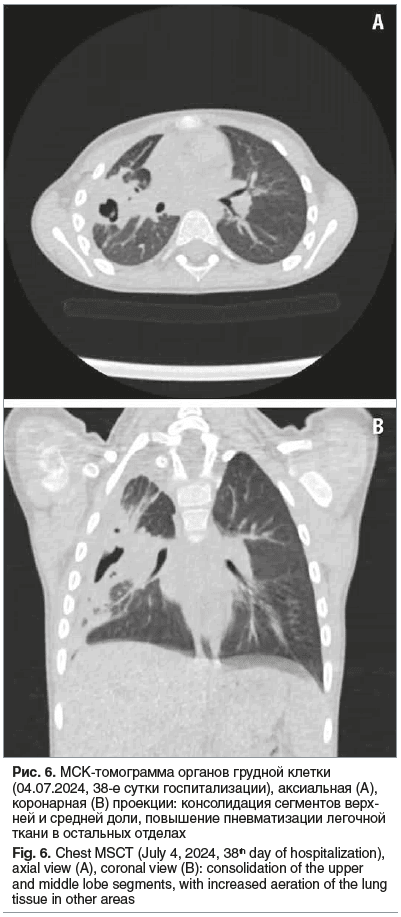

Постепенно на фоне проводимой терапии состояние ребенка улучшилось. Бронхоблокатор удален 24.06.2024 (33-и сутки заболевания). По данным МСКТ ОГП 04.07.2024 (38-е сутки госпитализации) сохранялась консолидация сегментов S1 и S3 справа, а также субплевральная консолидация сегментов S2, S4, S6. Воздушные полости с уменьшением в динамике. Неравномерное сужение верхнедолевого и сегментарных бронхов справа (рис. 6). Мальчик был выписан домой в удовлетворительном состоянии, продолжительность госпитализации составила 38 дней. За время болезни ребенок похудел на 4 кг (масса тела при выписке 12 кг). При выписке сохранялись редкий кашель, чувствительность в месте стояния дренажной трубки после ее удаления. Хронология течения болезни представлена на рисунке 7.